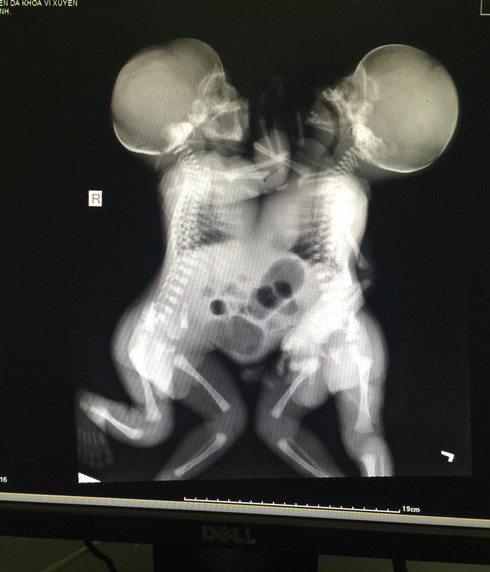

Hình ảnh hai bé bị dính một phần cơ thể. |

Lúc ấy các bác sĩ chỉ biết là thai đôi chứ không biết là hai thai dính nhau. Trong quá trình mổ sinh, bác sĩ phát hiện 2 bé trai dính liền với nhau từ ngực đến bụng, chung dây rốn, 2 thai có trọng lượng 4900gr.